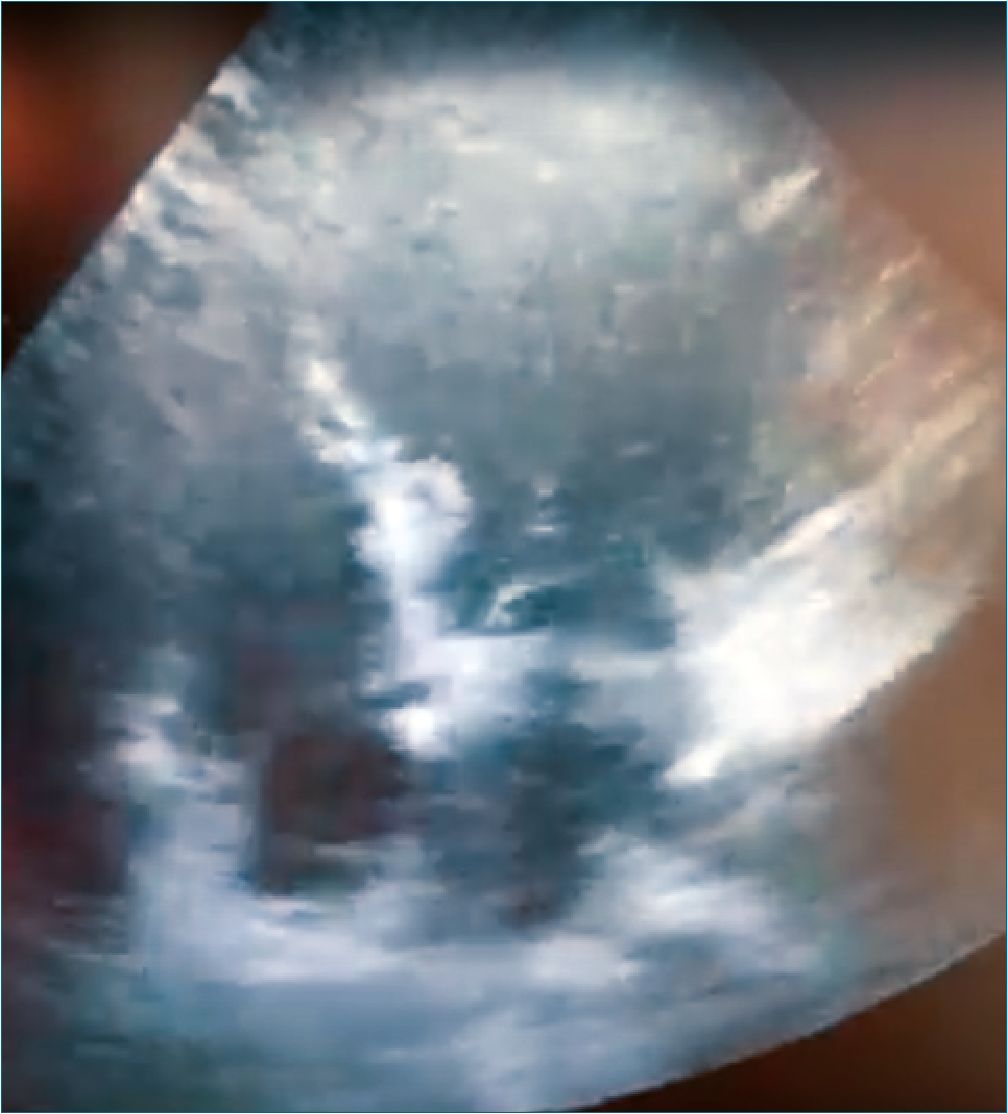

A transthoracic echocardiography was performed intraoperatively within 10 minutes after the dysrhythmia episode. In the 4-chamber view, generalized hypokinesis of the left ventricle (LV) with mild to moderate bulging was observed. Because the patient was undergoing surgery, it was not possible to obtain images from other views. It is worth highlighting that after the self-limited episode of arrhythmia, the patient’s clinical condition was stable. However, when considering the findings of the point of care echocardiogram, it was decided to extend the study by requesting troponins, evaluation by cardiology and a formal echocardiogram. At the end of the procedure, the patient was extubated and transferred to the post-anesthesia care unit, from where she was transferred to the ward, remaining stable and asymptomatic during this period and the rest of her hospital stay.

The following day after the cardiology assessment, a transthoracic echocardiogram was performed showing a mildly reduced LV ejection fraction (54%). The distal half of the LV was hypokinetic and there was compensatory hypercontractility of the basal segments. The pattern was suggestive of stress cardiomyopathy, (Figure 1) although left anterior descending artery (LAD) territory infarction could not be completely ruled out. Also, no significant valvular abnormalities. The Troponin T curve: Postoperative day (POD) 0: 258 ng/L, POD 1: 145 ng/L, POD 4: 27 ng/L. The report for the follow-up echocardiogram on POD 4 was: Normal left ventricular size and minimally reduced global systolic dysfunction (LVEF 53% by Simpson’s). Compared to previous TTE, it was described improvement in the stress cardiomyopathy. Cardiology indicated a coronary angiography for which the patient decided to be followed by her family doctor. She was discharged after a satisfactory postoperative course at POD 5.

Figure 1.